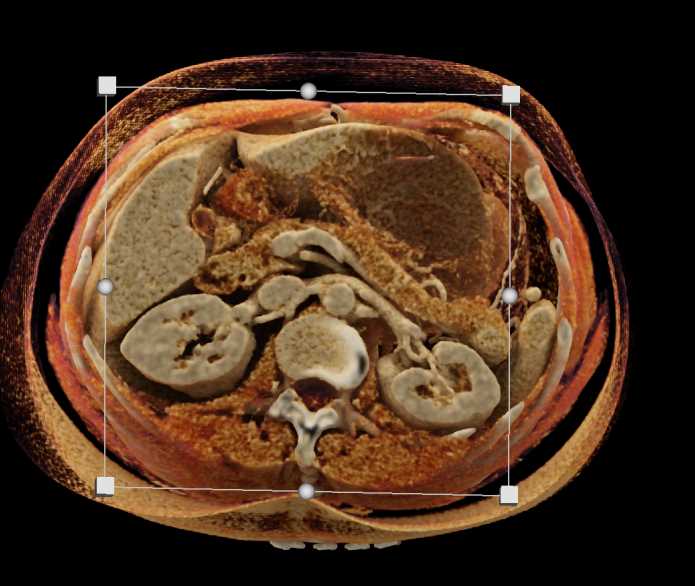

Gaucher's Spleen